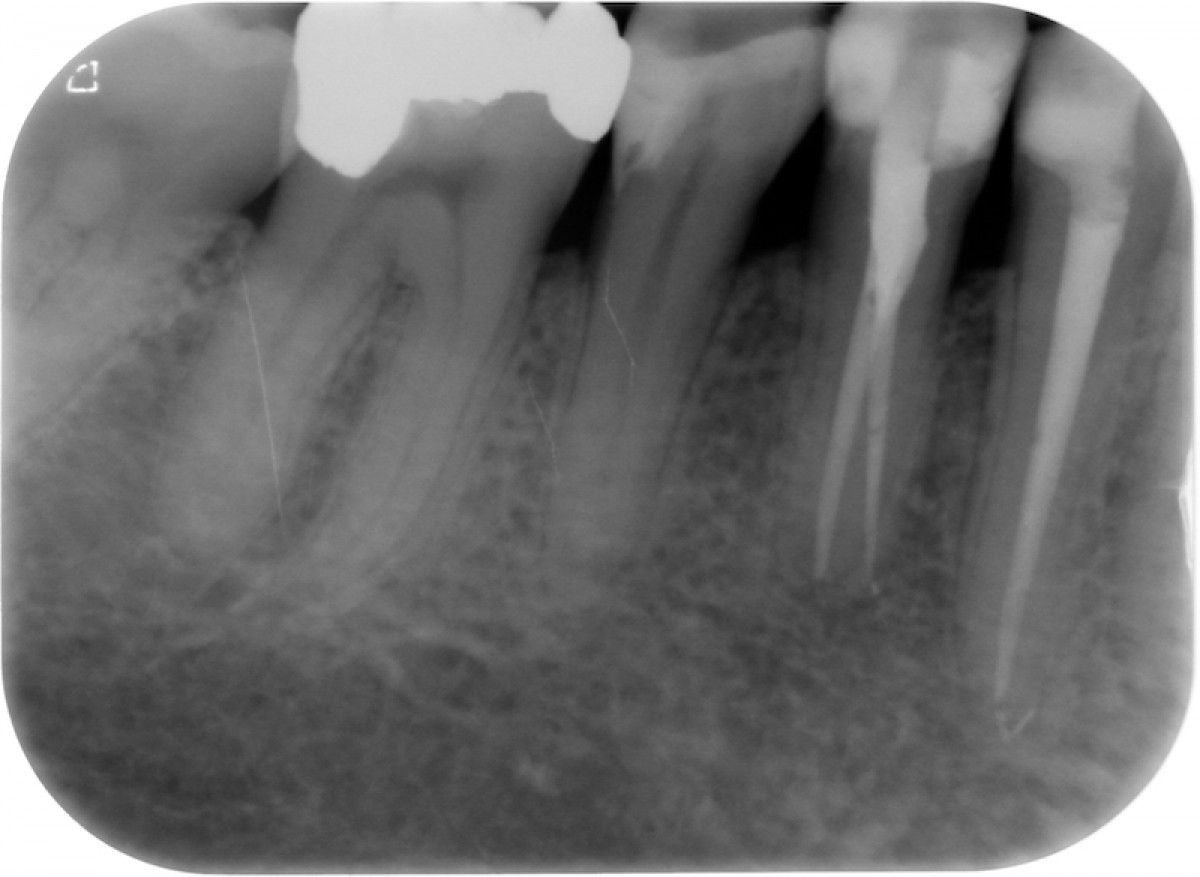

The gutta-percha point inserted into the root canal properly, adapting it to a size almost equal to the one employed to shape the apical terminus. Not wider, not smaller. Here are exposed a couple of cases made by shaping the root canal with a NiTi instrumentation technique and followed up for 9 to 12 months (Fig. 1-6).

It’s encouraging its easy handling and quite precise adaptation to the apical part of the root canal. The periapical healing, assessed by 2D-Rx, is considered satisfactory but further analysis and clinical studies related to these particular cements should be performed to confirm the first encouraging results.